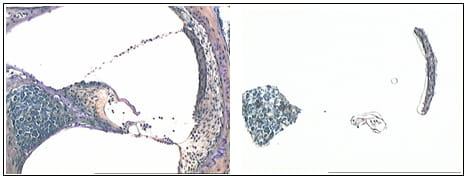

Laser capture microdissection: Sample here shows capture of cells from functional domains of the mouse cochlea.